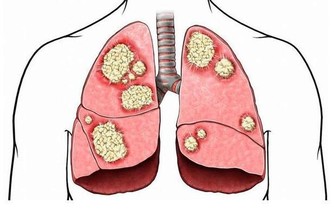

紅莧菜具有解毒清熱、補血止血、抗菌止瀉、消炎消腫、通利小便等功效;

莧科植物含有最豐富的生物鹼,所有現代人吃的肉和很多食物,會轉化成酸性物質。